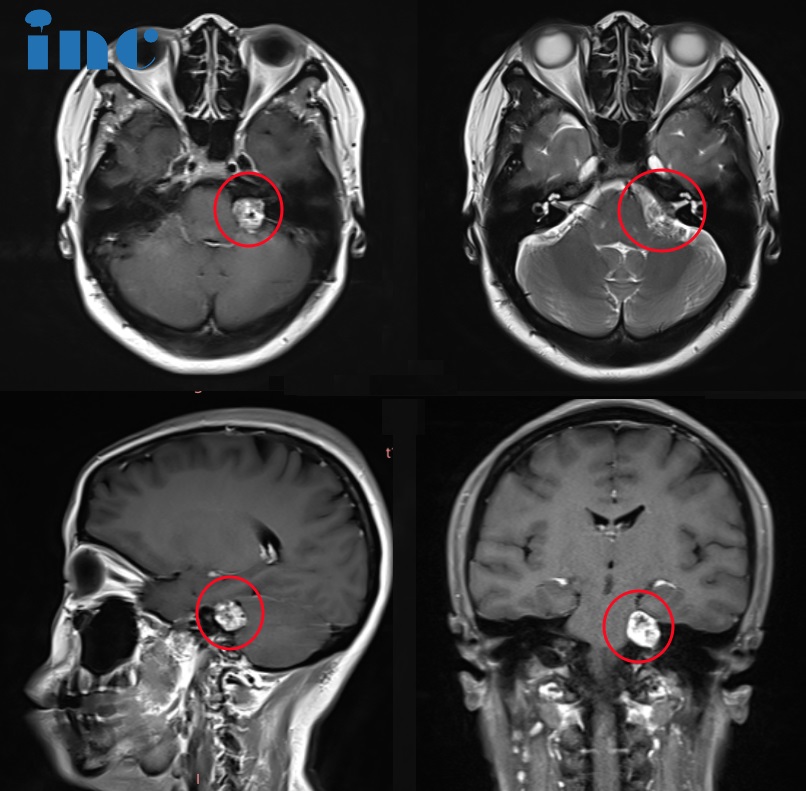

▼吳女士術(shù)前術(shù)后MRI對比顯示腫瘤得到全切

吳女士術(shù)前術(shù)后MRI對比顯示腫瘤得到全切

46歲的吳女士早在9月份就進(jìn)行了巴教授遠(yuǎn)程咨詢,提前預(yù)定這次天壇示范手術(shù)的寶貴機(jī)會。如今她終于等到這一天,巴教授為她順利全切聽神經(jīng)瘤,術(shù)后無新發(fā)神經(jīng)損傷,保留術(shù)前聽力、保留面神經(jīng)功能。術(shù)后一天巴教授查房時,已經(jīng)轉(zhuǎn)入普通病房的吳女士意識清楚、對答如流,“耳朵能聽到,臉能做表情,也不麻了”。吳女士無比感謝巴教授,術(shù)前她擔(dān)心的面癱、失聰都沒有發(fā)生,而一路陪伴在左右的愛人看到妻子恢復(fù)很好,也露出了幸福的笑容。

2023年7月以來,吳女士癥狀愈發(fā)嚴(yán)重,左側(cè)頭皮、臉頰、太陽穴、舌頭、嘴角發(fā)麻,左側(cè)頸部有沉重感、耳朵疼痛等等。然后前往醫(yī)院檢查才發(fā)現(xiàn)左側(cè)聽神經(jīng)瘤。吳女士術(shù)前已經(jīng)出現(xiàn)了輕微的腦干受壓,面部和三叉神經(jīng)受累的跡象(左嘴角刺痛等)以及聽力障礙。順利全切難度高,稍有不慎就可能導(dǎo)致面癱及失聰。但是不手術(shù),這個腫瘤已經(jīng)嚴(yán)重影響到吳女士的生活和工作。“下一步如何治療?真的無法順利全切腫瘤嗎?……”